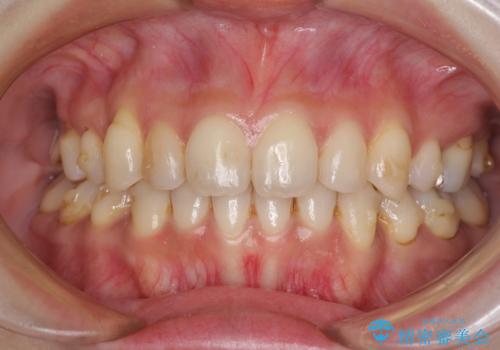

- 上下前歯の叢生を気にして来院された患者様です。

費用を抑え、期間もあまりかけずに治療をしたいとのことで、インビザライン・ライトを用いて矯正治療を行うこととしました。